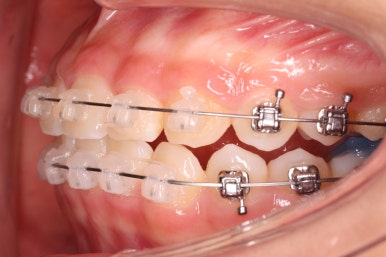

윗니에도 이제 장치를 모두 붙였습니다. 아래쪽은 어느 정도 가지런해지고 나면 부족한 자리를 만들어주기 시작합니다.

부산치아교정잘하는곳 키다리아저씨치과에서 이번 환자분에 사용한 장치는 데이몬 클리어라고 하는 세라믹 자가결찰 장치입니다. 세라믹 자가결찰 장치 중에서 철사를 잡아주는 CAP 부위까지 세라믹으로 되어있어 가장 심미적인 장치라고 볼 수 있습니다.

특히 웃을 때 철사 이외에는 장치가 크게 눈에 띄지 않아서 심미성을 원하시는 분들이 많이 선택을 하는 장치입니다.